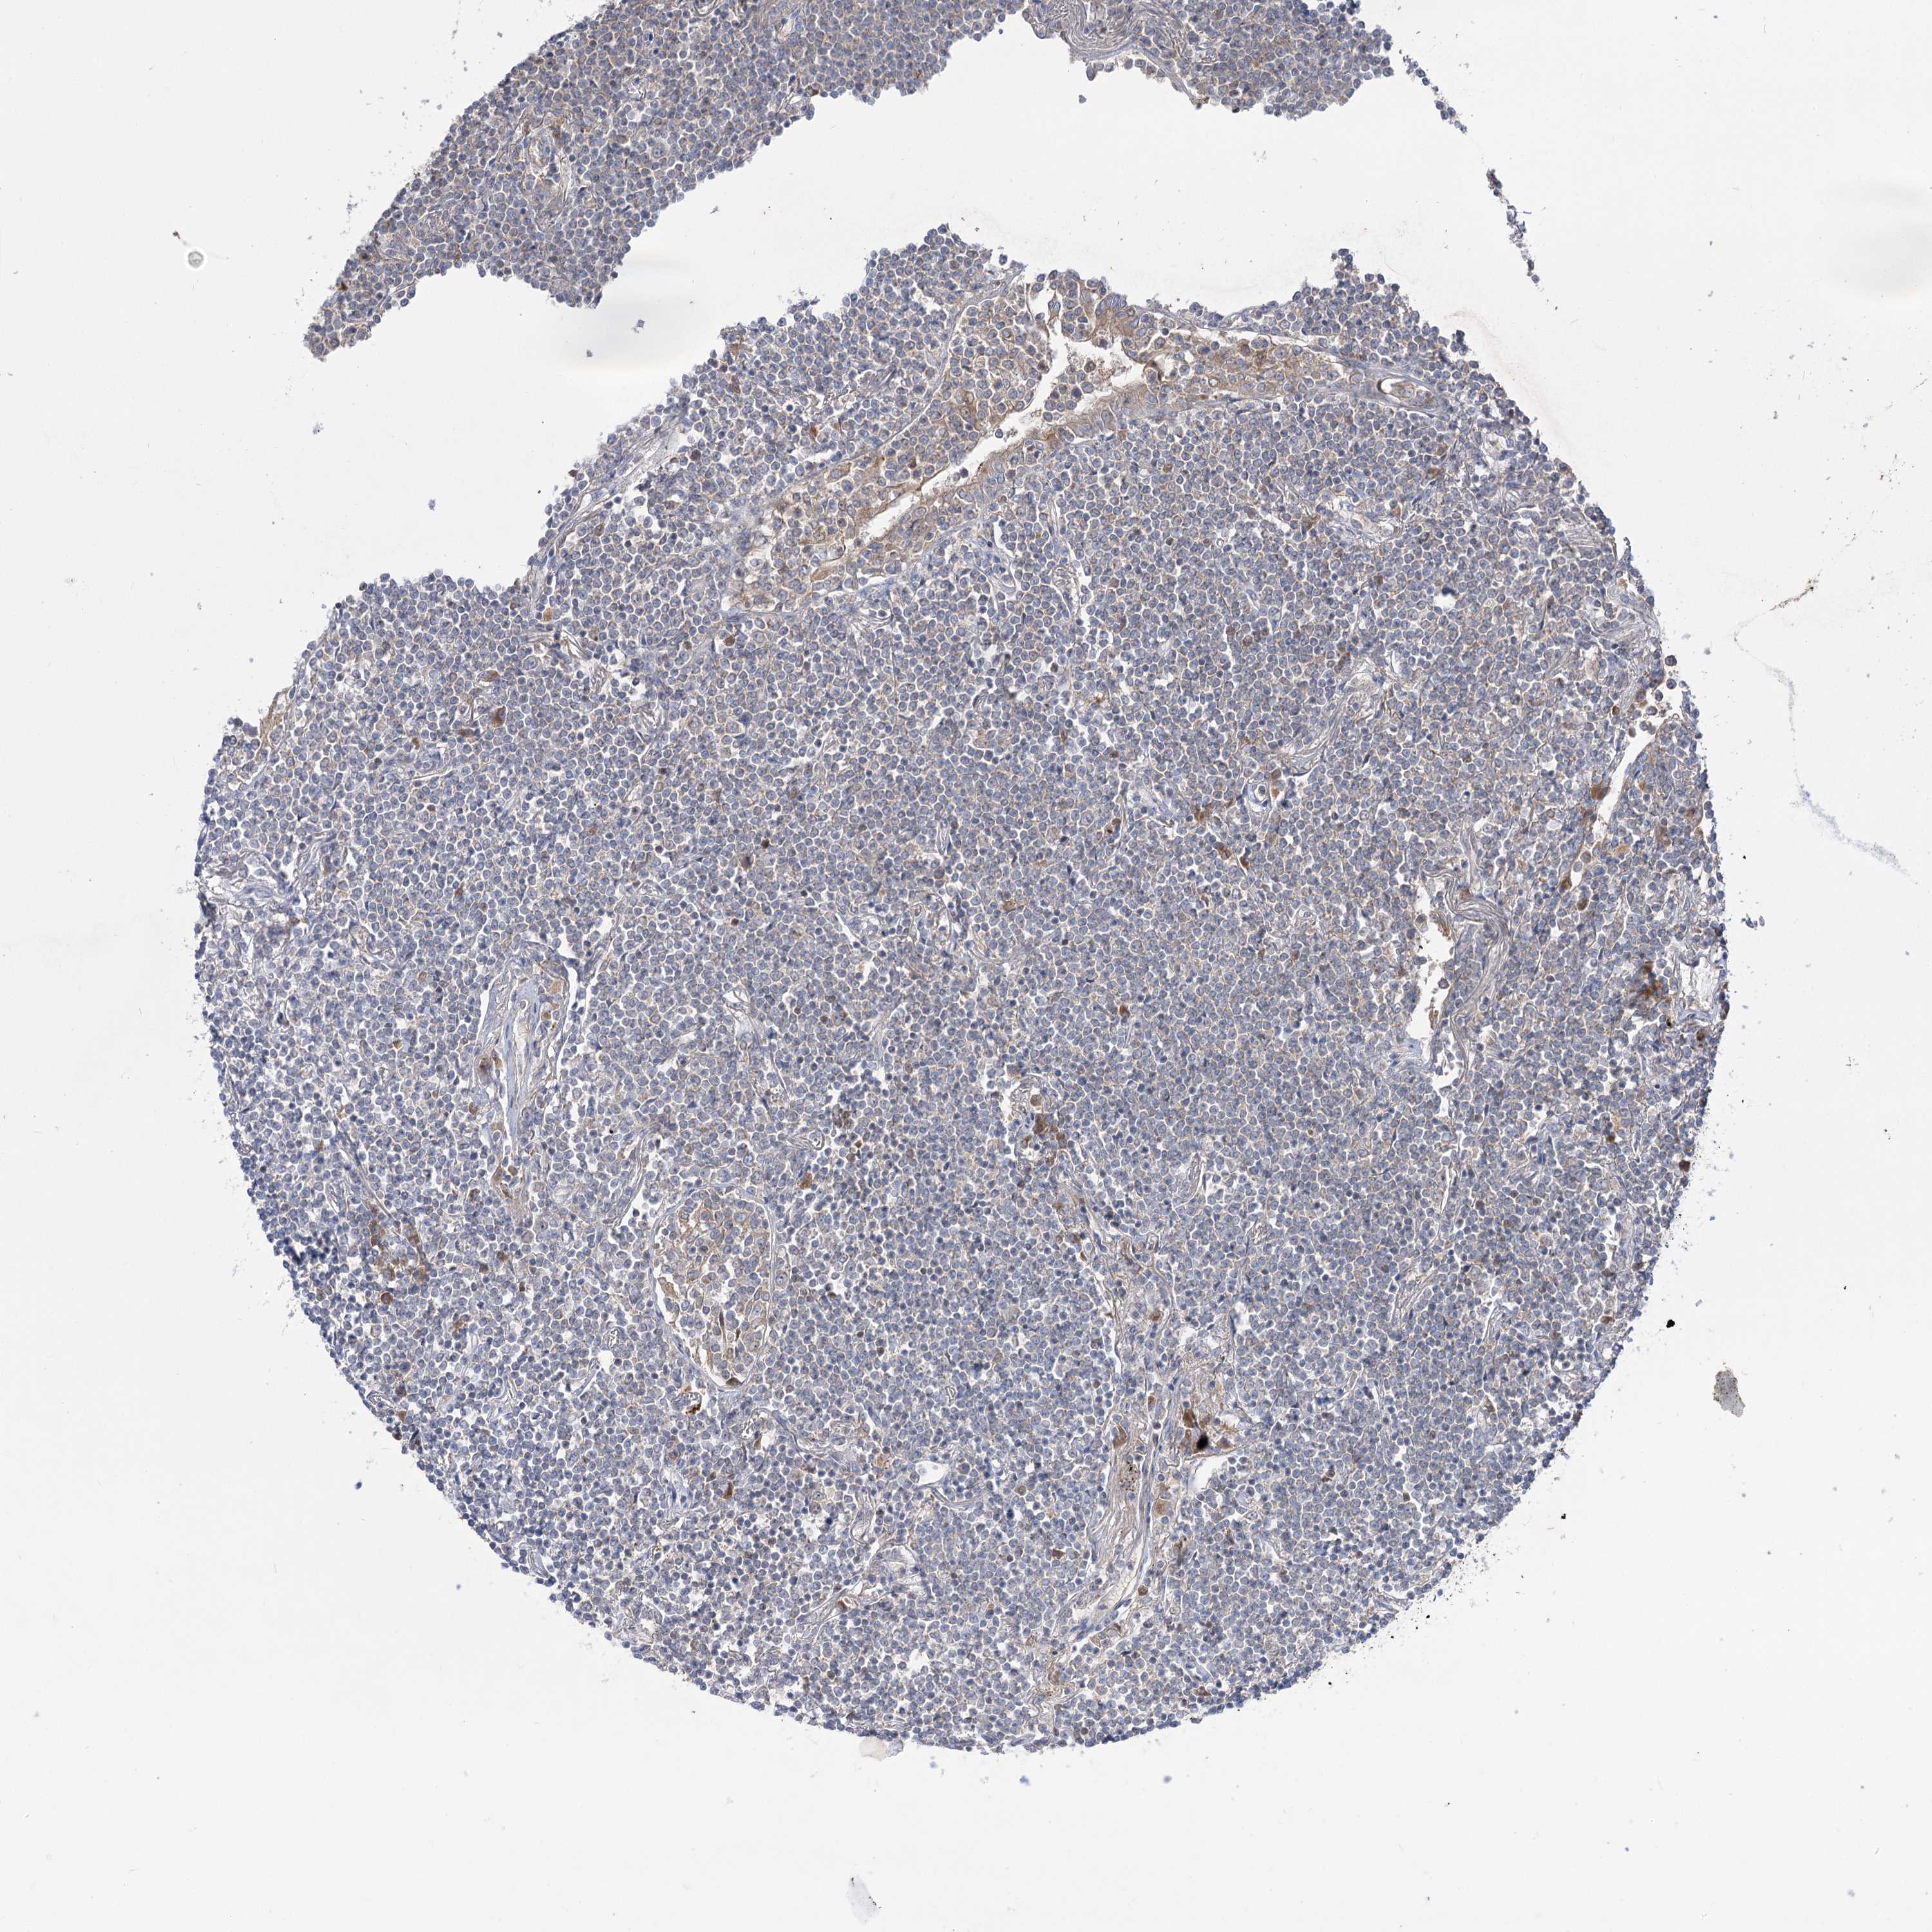

CANCER LYMPHOMA Show tissue menu

LYMPHOMA - Protein expressioni

A mouse-over function shows sample information and annotation data. Click on an image to view it in a full screen mode. Samples can be filtered based on level of antibody staining by selecting one or several of the following categories: high, medium, low and not detected. The assay and annotation is described here.

Antibody stainingi

Antibody staining in the annotated cell types in the current human tissue is reported as not detected, low, medium, or high, based on conventional immunohistochemistry profiling in selected tissues. This score is based on the combination of the staining intensity and fraction of stained cells.

Each image is clickable and will lead to virtual microscopy that enables deeper exploration of all samples and also displays staining intensity scores, fraction scores and subcellular localization as well as patient and tissue information for each sample.

Antibody HPA037759

Antibody HPA037760

Hodgkin's disease, NOS

Malignant lymphoma, non-Hodgkin's type, High grade

Malignant lymphoma, non-Hodgkin's type, Low grade